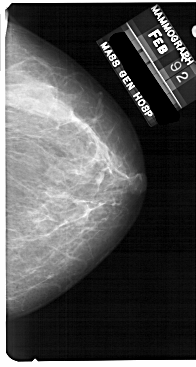

A_1710_1.RIGHT_CC

RIGHT_CC LINES 5491 PIXELS_PER_LINE 2926 BITS_PER_PIXEL 12 RESOLUTION 43.5 NON_OVERLAY